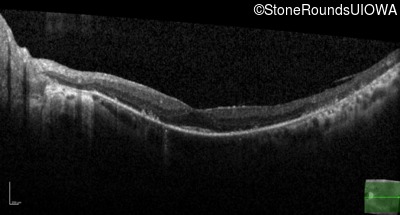

Optical Coherence Tomography - Left - 20/20 -2

Exemplar / OCT Stack

OCT Stack